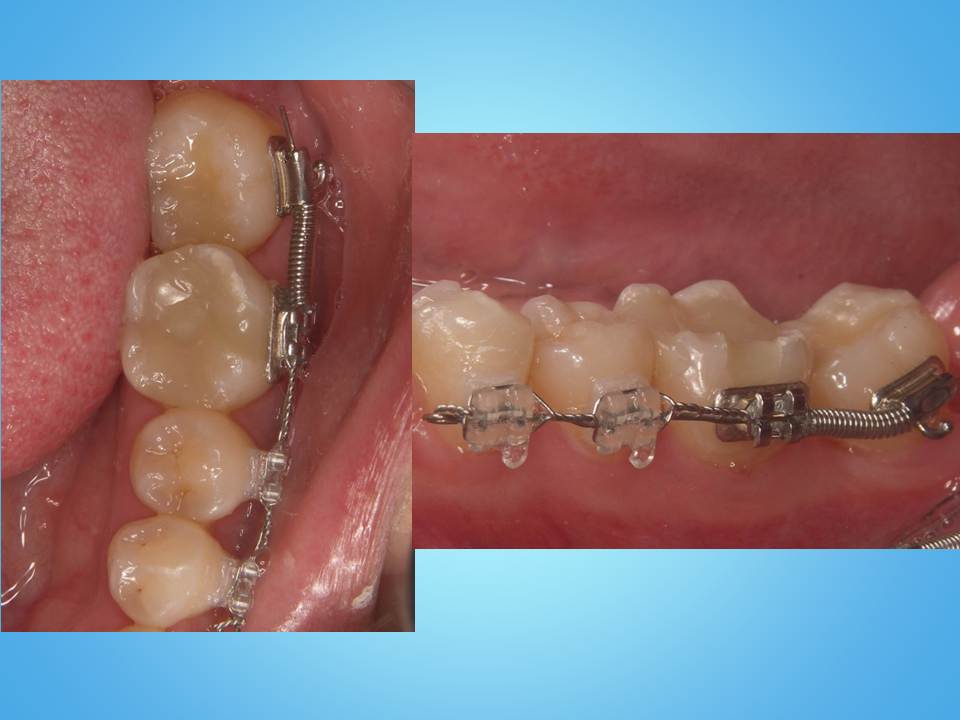

写真のように装置を取り付け、ワイヤーを使い引っぱり出す力を歯に伝えます。

矯正前と矯正後を比較すると、歯が引っぱり出されているのが確認できます。(黄色の線と赤の線の位置関係)